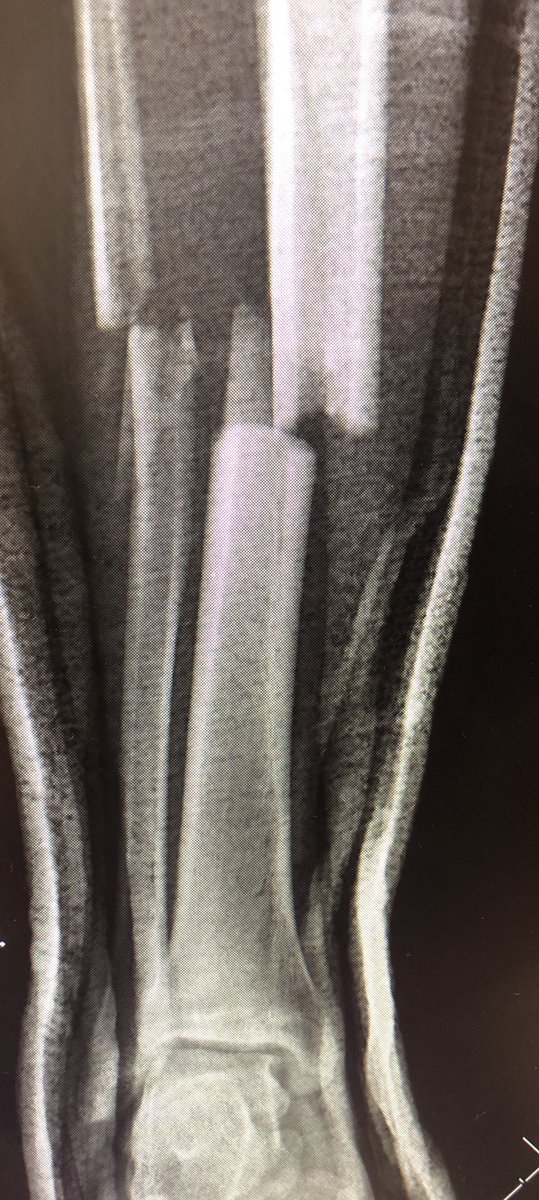

Good to hear @kalhourani1's paper on use of devitalised bone in open tibia fractures discussed in this evenings presentation by @HeidariN